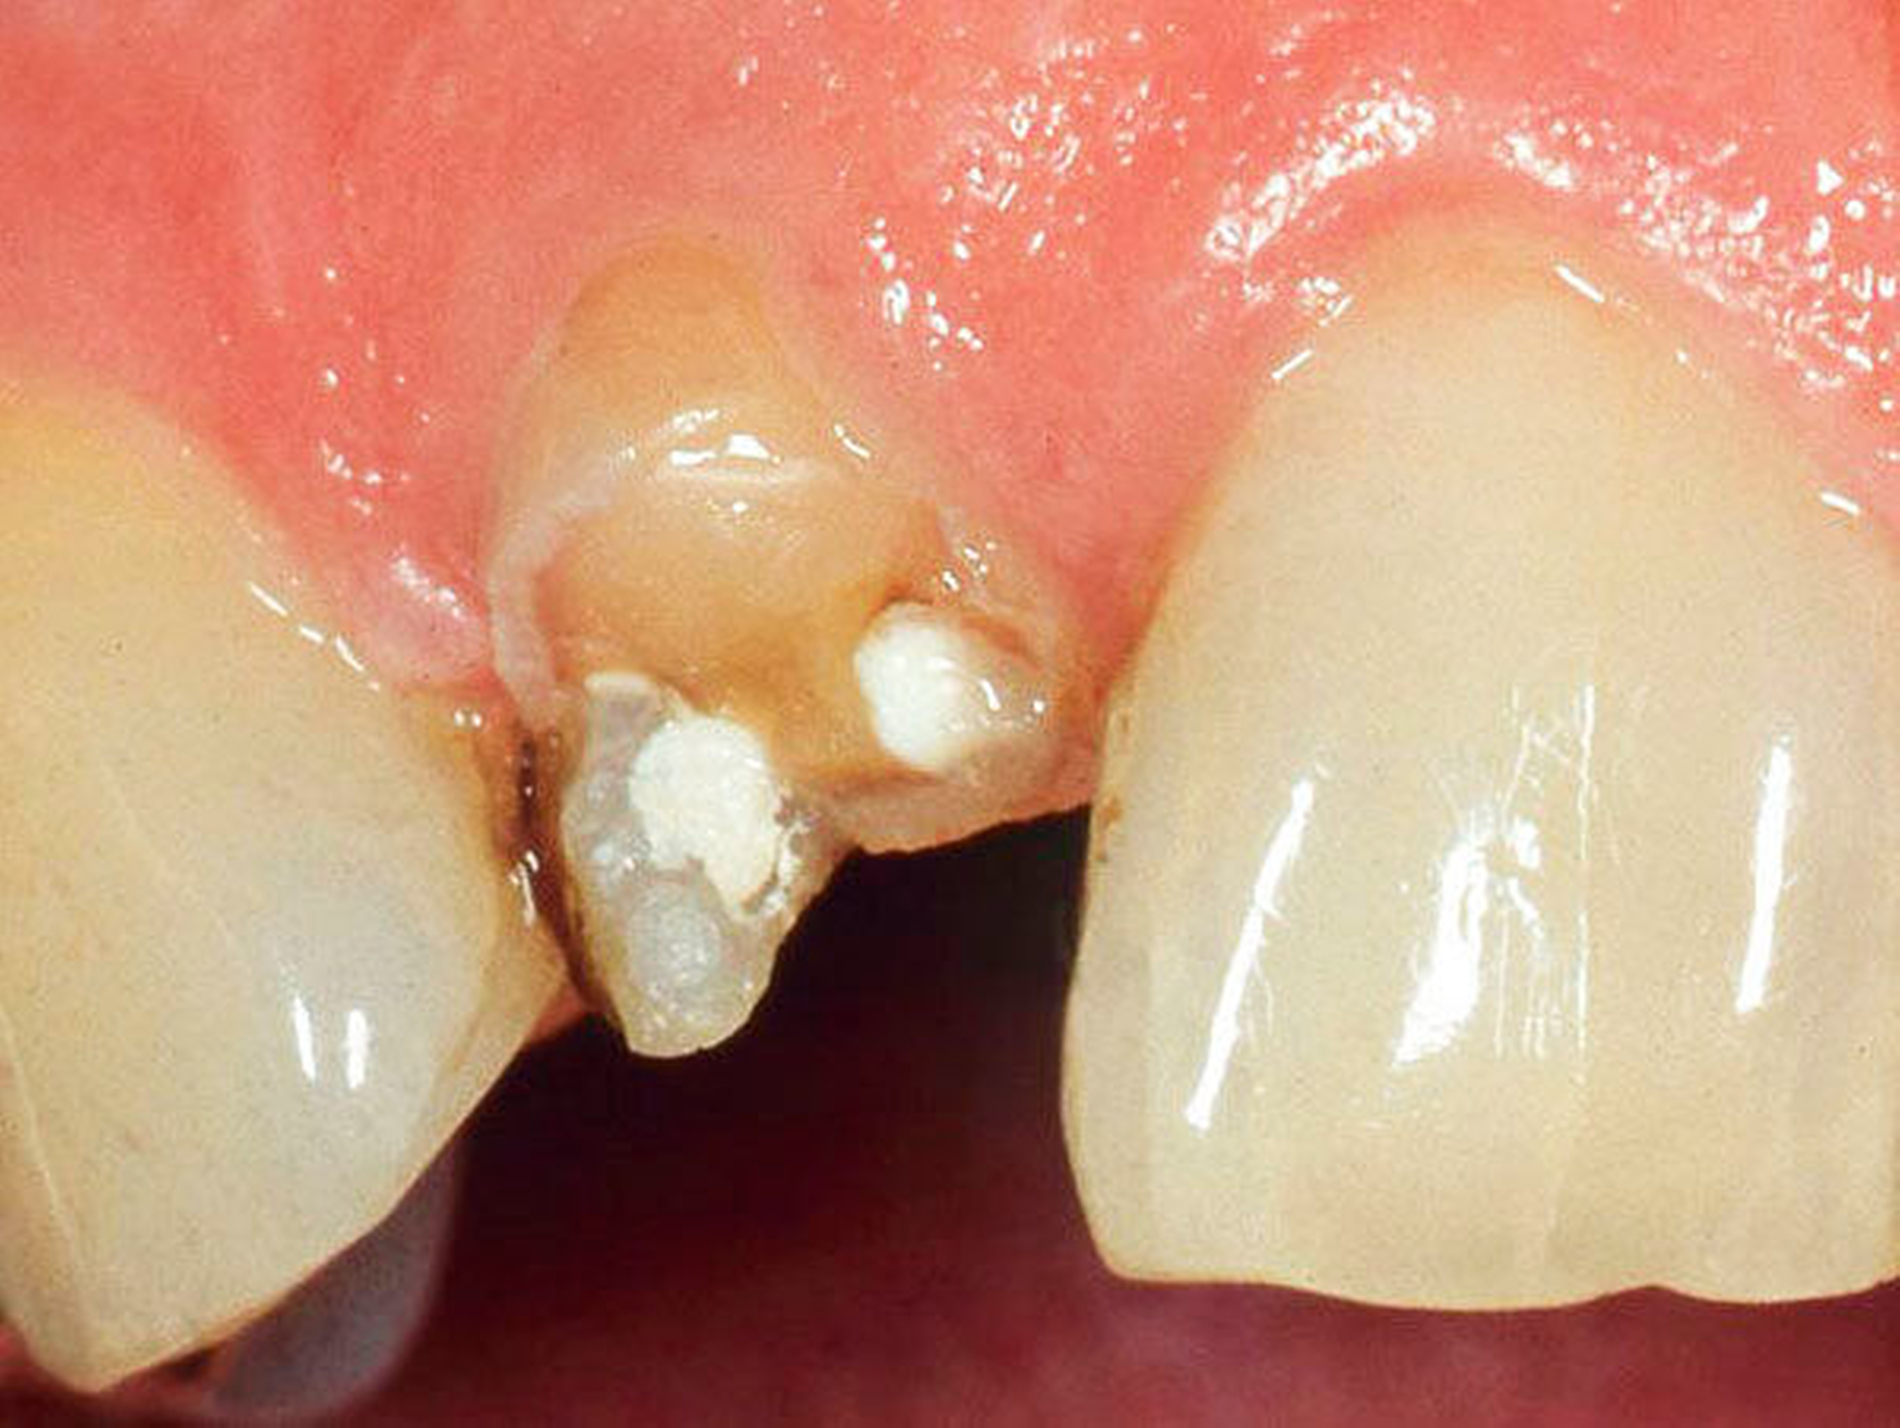

Abbildung 1a bis 1f: Direkte Überkronung im Frontzahnbereich (R1-Technik)

In den Abbildungen 1 bis 3 werden Optionen für frugale Interventionen auf restaurativem Sektor aufgeführt. Es handelt sich um direkte Vollüberkronungen im Frontzahnbereich (hier: hergestellt in R1-Technik / einphasig) (Abbildung 1), direkte Teilüberkronungen im Seitenzahnbereich (hier: hergestellt in R1-Technik / einphasig) (Abbildung 2), Reparatur-Restaurationen im Seitenzahnbereich (hier: hergestellt in R2-Technik / zweiphasig) (Abbildung 3). Technische Einzelheiten zur Vorgehensweise und den Ergebnissen sind an anderer Stelle beschrieben (Literatur siehe oben).

Am Beispiel von Abbildung 1 (stark zerstörte Zahnkrone eines Schneidezahns) kann das Prinzip der frugalen Intervention erläutert werden:

Früher wurde für die hier beschriebene Ausgangssituation folgendes Procedere gewählt:

Wurzelkanalbehandlung des vitalen Zahns als Voraussetzung für eine Stiftversorgung

Einsetzen eines Wurzelkanalstifts

Einsetzen einer indirekt gefertigten Stiftkrone

Durch die Erfolge der Adhäsiv- und Komposittechnik kann heute folgendermaßen vorgegangen werden:

Verzicht auf Wurzelkanalbehandlung / Erhaltung der Vitalität des Zahns

Verzicht auf Wurzelkanalstift

direkte minimalinvasive Kompositkrone (Verzicht auf indirekte Vorgehensweise)

Die potenziellen medizinischen und ökonomischen Vorteile dieser frugalen Intervention sind vielfältig:

Schonend: Die oralen Strukturen werden geschont und die Versorgung ist hinreichend stabil. Durch den Verzicht auf Wurzelkanalstifte wird das Wurzelfrakturrisiko reduziert. Zudem können Material-, Geräte- und Personalressourcen aus Praxis und Techniklabor, die beim klassischen Vorgehen anfielen, reduziert werden.

Bezahlbar: Hier ist anzumerken, dass die Kosten unter anderem von der zahnärztlichen Expertise abhängig sind: Zahnärzte, die mit direkten Restaurationen große Erfahrung haben, können zügiger und mit besserem Erfolg arbeiten als Kollegen mit geringerer Erfahrung auf diesem Gebiet; die Behandlung ist gleichwohl anspruchsvoll und deshalb nicht „billig“. Eine direkte Vorgehensweise kann, muss aber nicht automatisch zeit- und kostensparender sein als eine Versorgung mit indirekt hergestellten Werkstücken.

Gut genug: Ästhetische Feinheiten lassen sich bei direkten Restaurationen nicht immer in gleicher Perfektion einarbeiten wie bei indirekt gefertigten Kronen, auch die Stabilität des Hochglanzes lässt bei einigen Kompositpräparaten noch zu wünschen übrig. Andererseits erlauben die direkten Verfahren inzwischen mitunter sehr flexible Vorgehensweisen, die sich auch mit Farb- und Formkorrekturen von Zähnen kombinieren lassen. Die Erwartungen eines großen Teils der Patienten werden hinreichend erfüllt und die Nutzen-Risiko-Relationen wie auch die Aufwand-Kosten-Relationen erscheinen – wenn auch nicht durchgängig – so doch zumindest in vielen Fällen günstig.